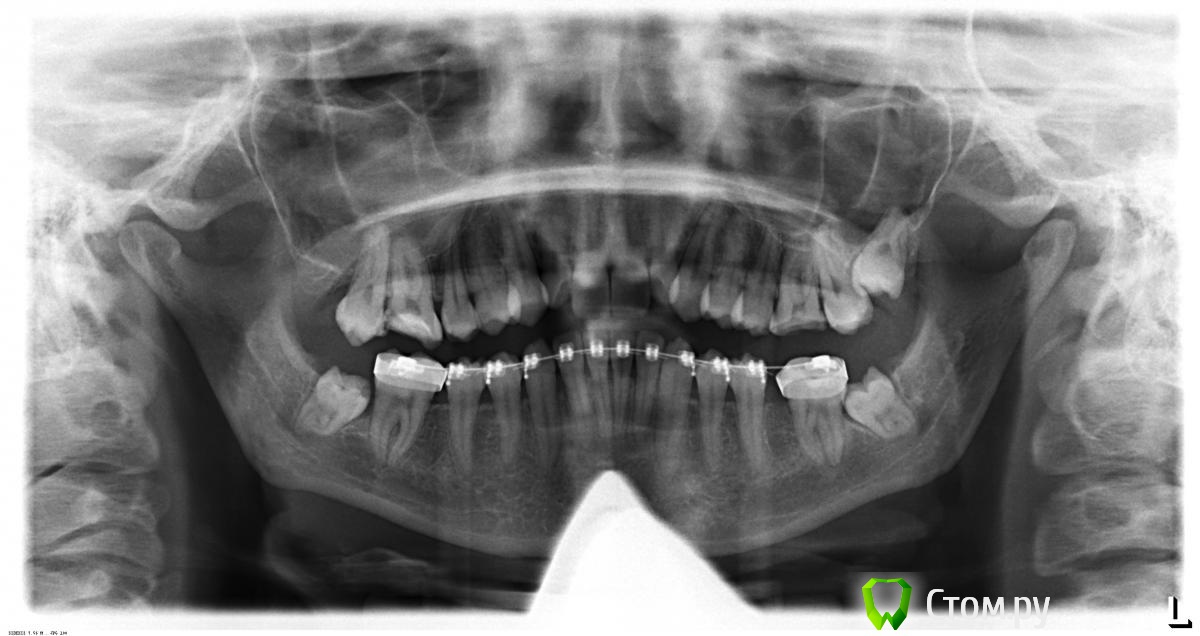

innessa Опубликовано 23 апреля, 2014 Поделиться Опубликовано 23 апреля, 2014 Здравствуйте. Ищу помощи и возможности принять правильное решение в лице стом.ру. Моя ситуация такова: мне 23 года, 1 год и 4 мес. прошло с тех пор, как мне установили брекет систему на нижнюю челюсть, перед этим удалив нижние шестые зубы. На ОПТГ картина 1 мес. назад.мой доктор-ортодонт рекомендует мне теперь удалить верхние четвертые зубы и продолжать ортодонтическое лечение.Что меня беспокоит, четвертые зубы абсолютно здоровы, в отличии от шестых и седьмых ( верхняя челюсть); была на консульт. и у других специалистов этой отрасли- у каждого свое мнение по поводу дальнейшего плана лечения и все они разные. помогите принять верное решение! Ссылка на комментарий

innessa Опубликовано 24 апреля, 2014 Автор Поделиться Опубликовано 24 апреля, 2014 трг и оптг Ссылка на комментарий

m.d.n Опубликовано 25 апреля, 2014 Поделиться Опубликовано 25 апреля, 2014 Поместите ссылку чтобы можно было скачать файл. Надо увидеть не что нибудь а иметь исходный файл снимка вашего чтобы провести его анализ. У вас вертикальный тип роста и как мне кажется верх и низ в ретро положении. Будет снимок скажу больше. Я могу вам порекомендовать только сменить доктора . я ведь вас не вылечу через форум. Ссылка на комментарий